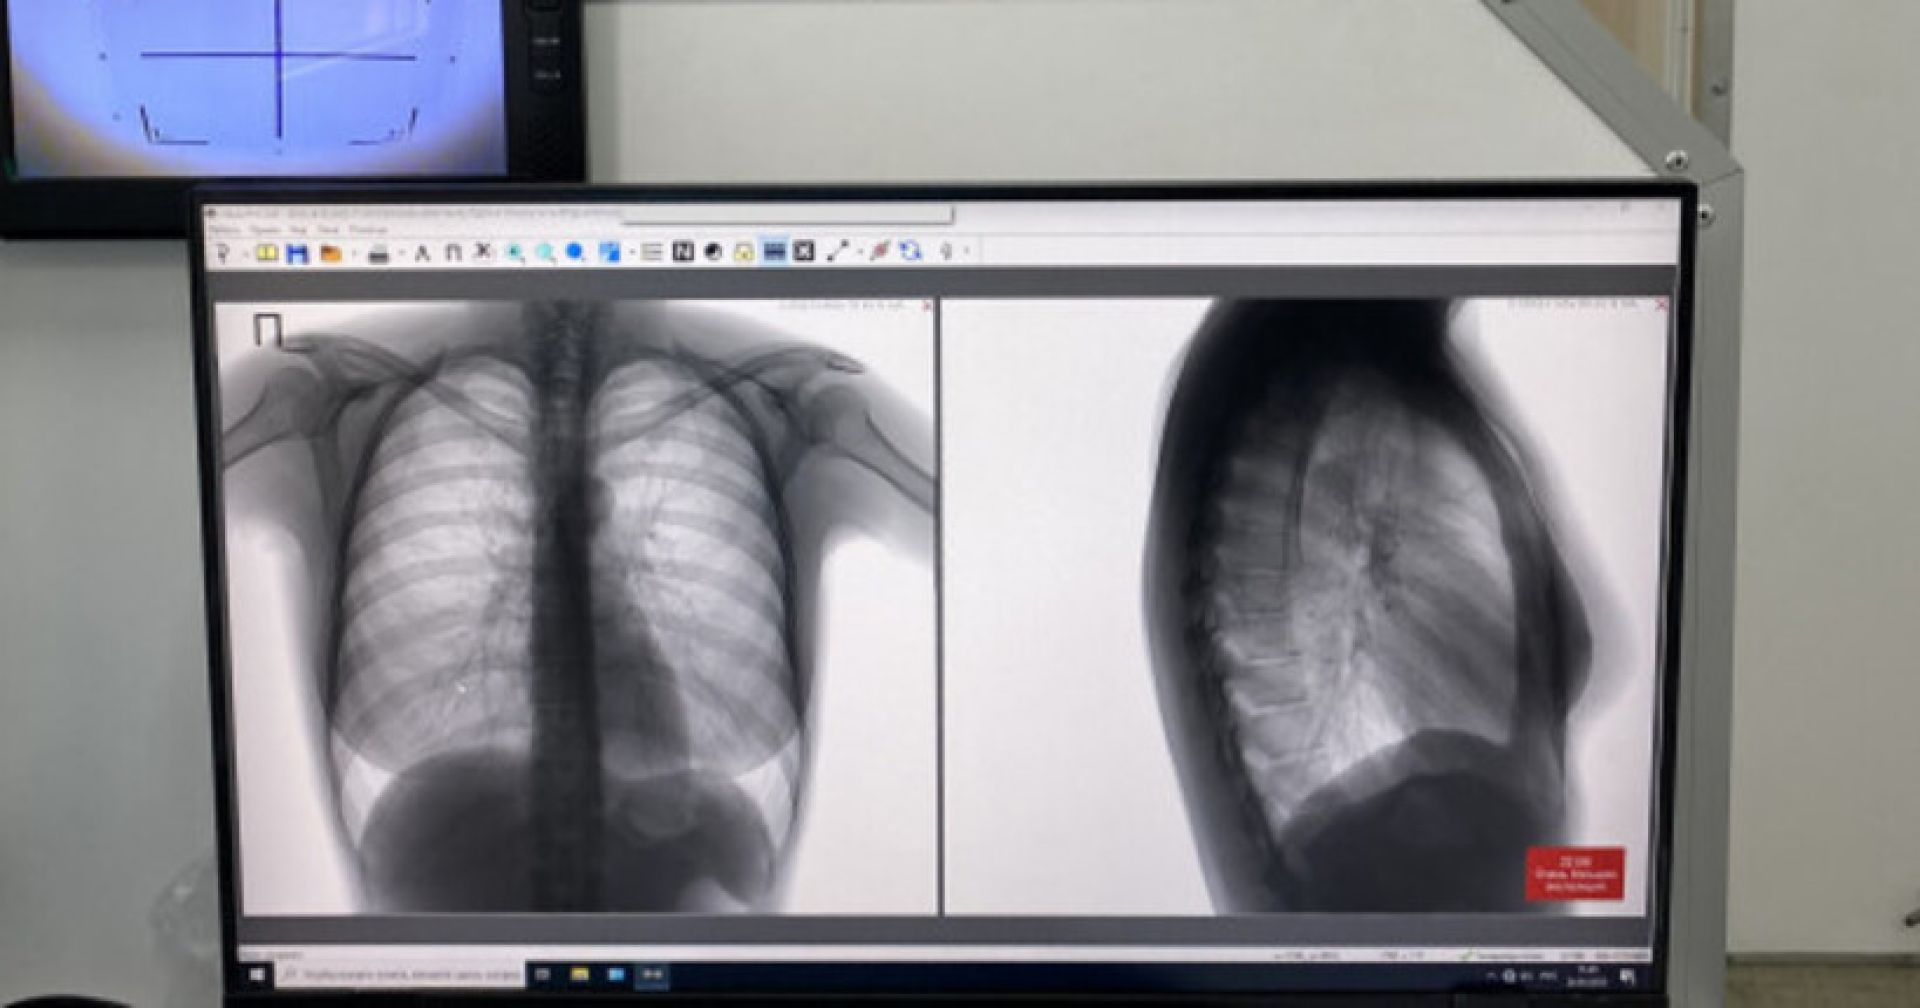

В Новосибирской области снизилась заболеваемость туберкулёзом

По словам замминистра здравоохранения региона Елены Аксёновой, в 2023 году первичный диагноз «туберкулёз» поставили 1418 новосибирцам, по итогам 2025 года эта цифра сократилась до 1153. Снизилось также количество пациентов, состоящих на диспансерном учёте — за два года их стало меньше почти на две тысячи человек.

— В течение последних лет был увеличен охват иммунодиагностикой, на хорошем уровне флюорографические обследования. В рамках нацпроектов медорганизации области были оборудованы современными цифровыми флюорографами, передвижными мобильными комплексами. Кроме того, прошла большая реорганизация фтизиатрической службы, — сообщила Елена Аксёнова.

В свою очередь главврач Новосибирской областной клинической туберкулёзной больницы Анна Пятибратова отметила, что заболеваемость снизилась почти на 7%, а смертность — на 9%.